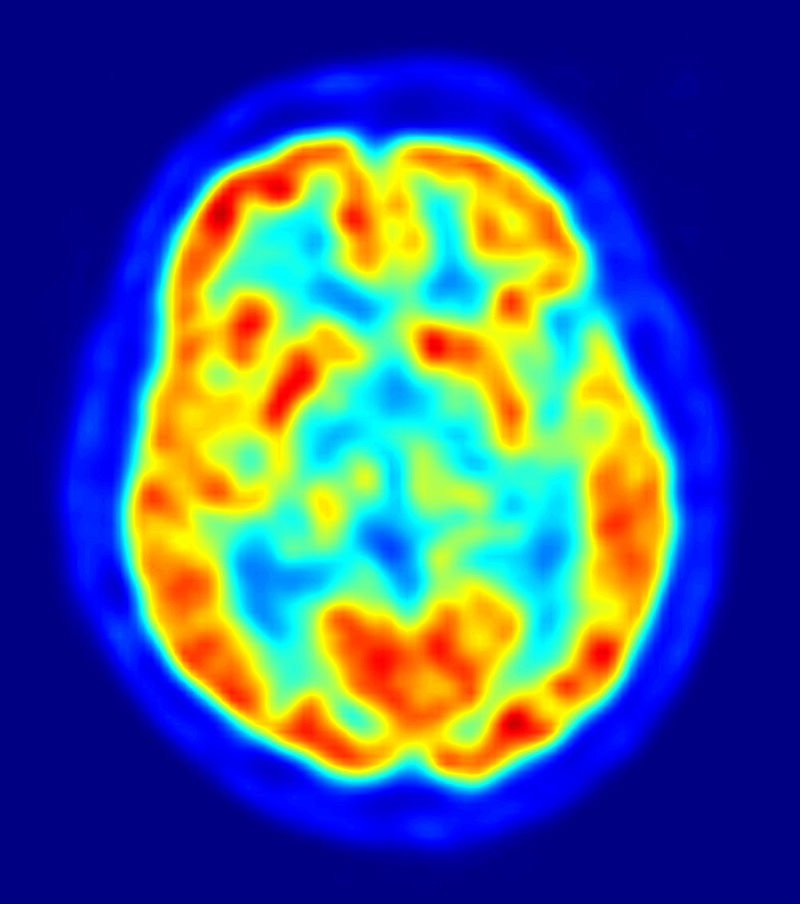

ElMindA’s Brain Network Activity system is used to analyse neural processes, with the potential to reveal brain problems early on and thus increase the efficacy of treatment for disorders such as Alzheimer’s and Parkinson’s disease. Earlier this month, the United States Food and Drug Administration cleared ElMindA’s BNA™ Analysis System for the assessment of brain function in 18-24 year olds. Jeffrey S. Kutcher, M.D., associate professor of neurology, University of Michigan Medical School has noted that ElMindA “will allow those of us caring for patients the ability to more clearly differentiate a healthy brain from one affected by disease or injury, and potentially have more informed discussions about lifestyle, activity, prevention and treatment decisions as a result.”

This is a highly innovative technology, not just in its ability to provide doctors with a comprehensive view of brain health, but in the sense that unlike similar technologies, it does not require penetration of the skull, instead taking measurements via a sensor-laden ‘helmet’. This system is fitted with numerous electrodes that measure brain activity. The data drawn from its interaction with a user’s brain functions is analysed by specially-developed algorithms that work to reveal neural pathways. This data is able to assist doctors in understanding of brain functionality, following disease progression and measuring responses to medical intervention.